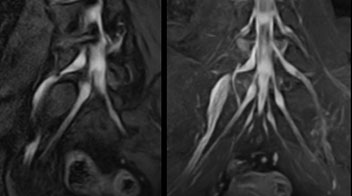

“NerveVIEW can clearly show nerve courses and presence of nerve compression. However, when multiple abnormalities are seen, it can still be hard to determine which nerve is causing the symptoms,” says Dr. Yabuki. “In our experience so far, we see abnormal findings on NerveVIEW in about 70% of elderly patients. As the pain is usually caused by only one nerve, we thus need to find the exact corresponding nerve.” “With a nerve root block, the patient's pain is improved by infiltration of local anesthesia directly around the nerve root considered to be responsible. Knowing such nerve root block findings prior to image interpretation, helps to easily recognize abnormal findings on NerveVIEW as well. In other words, without a priori knowledge, based on symptoms and/or nerve root block findings, we must be aware of the possibility of overdiagnosis.”

The addition of the nerve-selective NerveVIEW sequence to its spine MRI protocol has given NFMC competitive advantages, according to Tanji. “Since we started including NerveVIEW routinely, the demand for lumbar spine MRI examinations has increased, especially for pre-surgical planning purposes and for patients with chronic lower extremity symptoms,” he says. “Moreover, because no other hospitals in our region are doing nerve plexus imaging yet, we often receive referrals for MR neurography studies from other hospitals even if they have an MRI scanner. Some requests come from as far as 100 km away. NerveVIEW definitely provides us a competitive advantage.” “Based on our experience, we can certainly recommend NerveVIEW to other centers,” Dr. Yabuki adds. “The sequence opens up many possibilities to facilitate the diagnosis of lower extremity pain and to inform our decision-making regarding therapy and surgery.”

Implementing NerveVIEW without lengthening exam time “The source images of NerveVIEW exhibit a contrast similar to STIR or fat-suppressed T2-weighted images. So, in our neurography exams we are replacing the 2D T2-weighted coronal sequence with 3D NerveVIEW. With this, we add a lot of useful information without adding scan time. This is important for patients with severe lower extremity symptoms, as they often find it difficult to maintain still during the whole MRI examination, so the exam should be as short as possible.” “We have currently implemented 3D NerveVIEW on our Achieva 3.0T dStream MRI system only. Because the 3D NerveVIEW method is based on a background signal suppression technique, we decided to use the high SNR of our 3.0T MRI system for obtaining the best possible visualization of peripheral nerves,” says Tanji. “Where NerveVIEW of the lumbar plexus is currently used as a subroutine scan for patients with strong lower limb symptoms, its use for visualization of the brachial plexus, is currently limited to special cases such as schwannomas and neuritis, usually only 1 or 2 cases per month.”